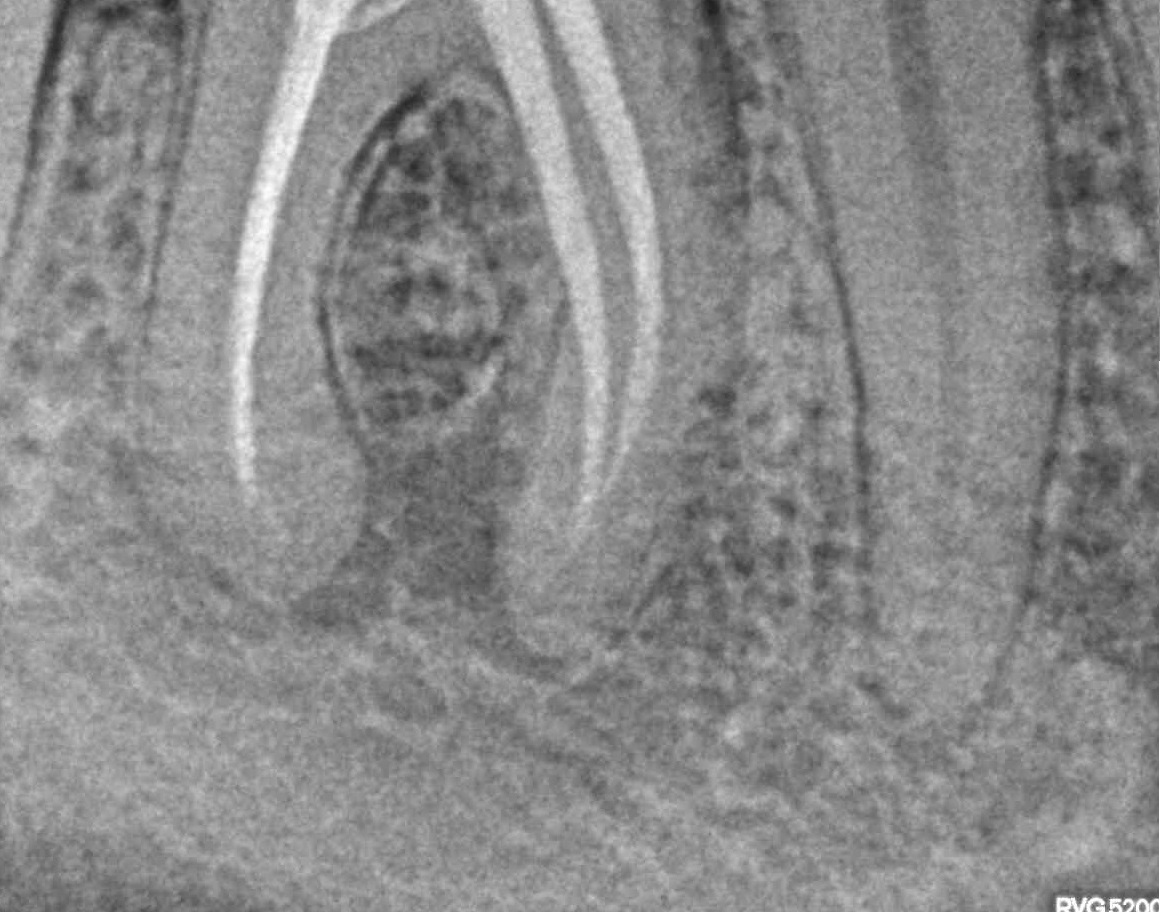

- Лечение периодонтита

Проблема

Пациент обратился в клинику с постоянными ноющими самопроизвольными болями в зубе, усиливающиеся при накусывании, отечность тканей в области причинного зуба. После детального обследования были обнаружены значительные очаги воспаления на корнях зуба.Решение

Пациенту было проведено эндодонтическое лечение данного зуба. В результате лечения наблюдаем восстановление костной ткани, окружающей зуб.